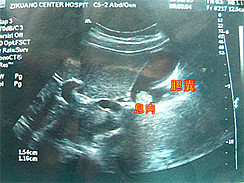

胆囊结石的诊断主要依靠病史和超声检查,通常容易确诊。

1、 超声检查